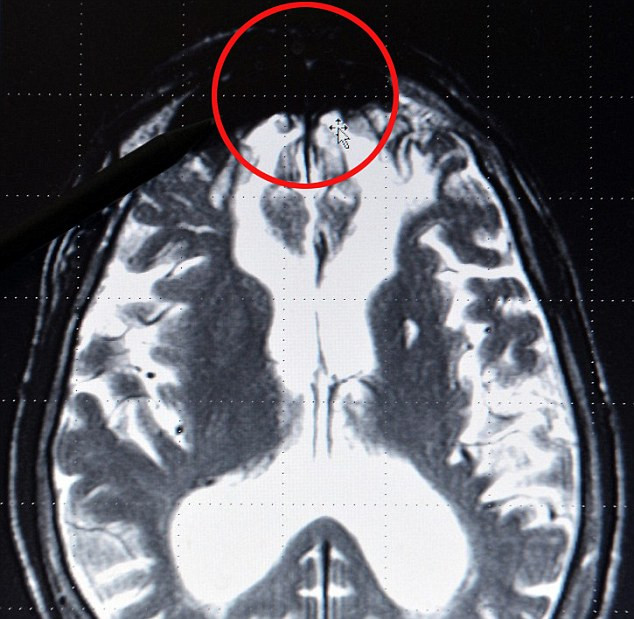

Un neurolog german susţine că a descoperit regiunea din creier asociată cu comiterea de activităţi infracţionale, acea zonă având o culoare întunecată în cazul criminalilor, al violatorilor şi al hoţilor.

Medicul Gerhard Roth din Bremen susţine că "regiunea răului" se află în lobul cerebral central şi apare pe radiografii sub forma unei mase întunecate, informează dailymail.co.uk.

Acea masă întunecată, aflată în partea din faţă a creierului, a apărut în toate tomografiile persoanelor care au comis acte de violenţă criminală.

"Atunci când primeşti radiografiile creierelor unor criminali periculoşi, se observă aproape întotdeauna anumite deficienţe în partea din faţă a creierului.

Există cazuri când anumiţi oameni devin infractori din cauza unei tumori sau a unei leziuni din acea zonă, iar după operaţia de îndepărtare a tumorii, acea persoană devine din nou un om normal.

Acestea sunt deficienţe fiziologice, întrucât anumite substanţe, precum serotonina din lobul frontal, nu lucrează eficient. Însă aceasta este cu siguranţă zona cerebrală unde se formează răul şi unde acesta stă ascuns", a explicat savantul german.

"Desigur, nu este ceva automat. Creierul poate să compenseze cumva tendinţele violente, însă nu se ştie cum procedează. Însă, atunci când văd tomografia unui tânăr şi descoper deficienţe în lobul frontal, îmi spun că există un risc de 66% ca acea persoană să fie un infractor în devenire. E uşor să descoperi comportamentul antisocial foarte devreme", a adăugat el.